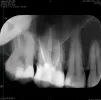

В августе пролечил пульпит верхней 6-ки справа с пломбировкой 3-х каналов. Существует небольшая чувствительность зуба ночью и утром.

Правильно ли выполнена пломбировка и есть ли там еще 4-й канал? Есть ли кариес на 37 зубе?

Судя по данному снимку, каналы верхнего шестого зуба запломбированы хорошо. Если судить очень строго, то каналы щечных корней на отлично, а канал небного корня немного недопломбирован, но никаких изменений в периодонте нет. Периодонт - это связка зуба, удерживающая его в лунке и выполняющая ряд других немаловажных функций.

Возможно, стоит дать время зубу. Пломба в полном порядке, насколько позволяет судить данный снимок.